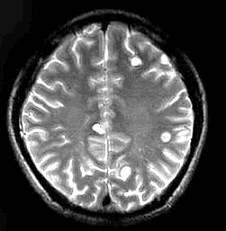

男,29岁。头痛不适半个月。MRI扫描如图示。据此可作出以下最可能的诊断是()

A.脑转移瘤

B.脑囊虫病

C.脑弓形虫病

D.脑脓肿

E.未见异常

[单选题]男,29岁,头痛不适半个月,MRI扫描如图,最可能的诊断是()A.脑转移瘤B.脑囊虫病C.脑弓形虫病D.脑脓肿E.未见异常

[单选题]男,29岁。头痛不适半个月。MRI扫描如图示。据此可作出以下最可能的诊断是()A . 脑转移瘤B . 脑囊虫病C . 脑弓形虫病D . 脑脓肿E . 未见异常

[单选题]男,29岁。头痛不适半个月。MRI扫描如图示。据此可作出以下最可能的诊断是()A .脑转移瘤B .脑囊虫病C .脑弓形虫病D .脑脓肿E .未见异常

男,29岁,头痛不适半个月,MRI扫描如图,最可能的诊断是()

[单选题]男,29岁,头痛不适半个月,MRI扫描如图,最可能的诊断是()A . 脑转移瘤B . 脑囊虫病C . 脑弓形虫病D . 脑脓肿E . 未见异常

男,29岁,头痛不适半个月,MRI扫描如图,最可能的诊断是()

[单选题]男,29岁,头痛不适半个月,MRI扫描如图,最可能的诊断是()A .脑转移瘤B .脑囊虫病C .脑弓形虫病D .脑脓肿E .未见异常